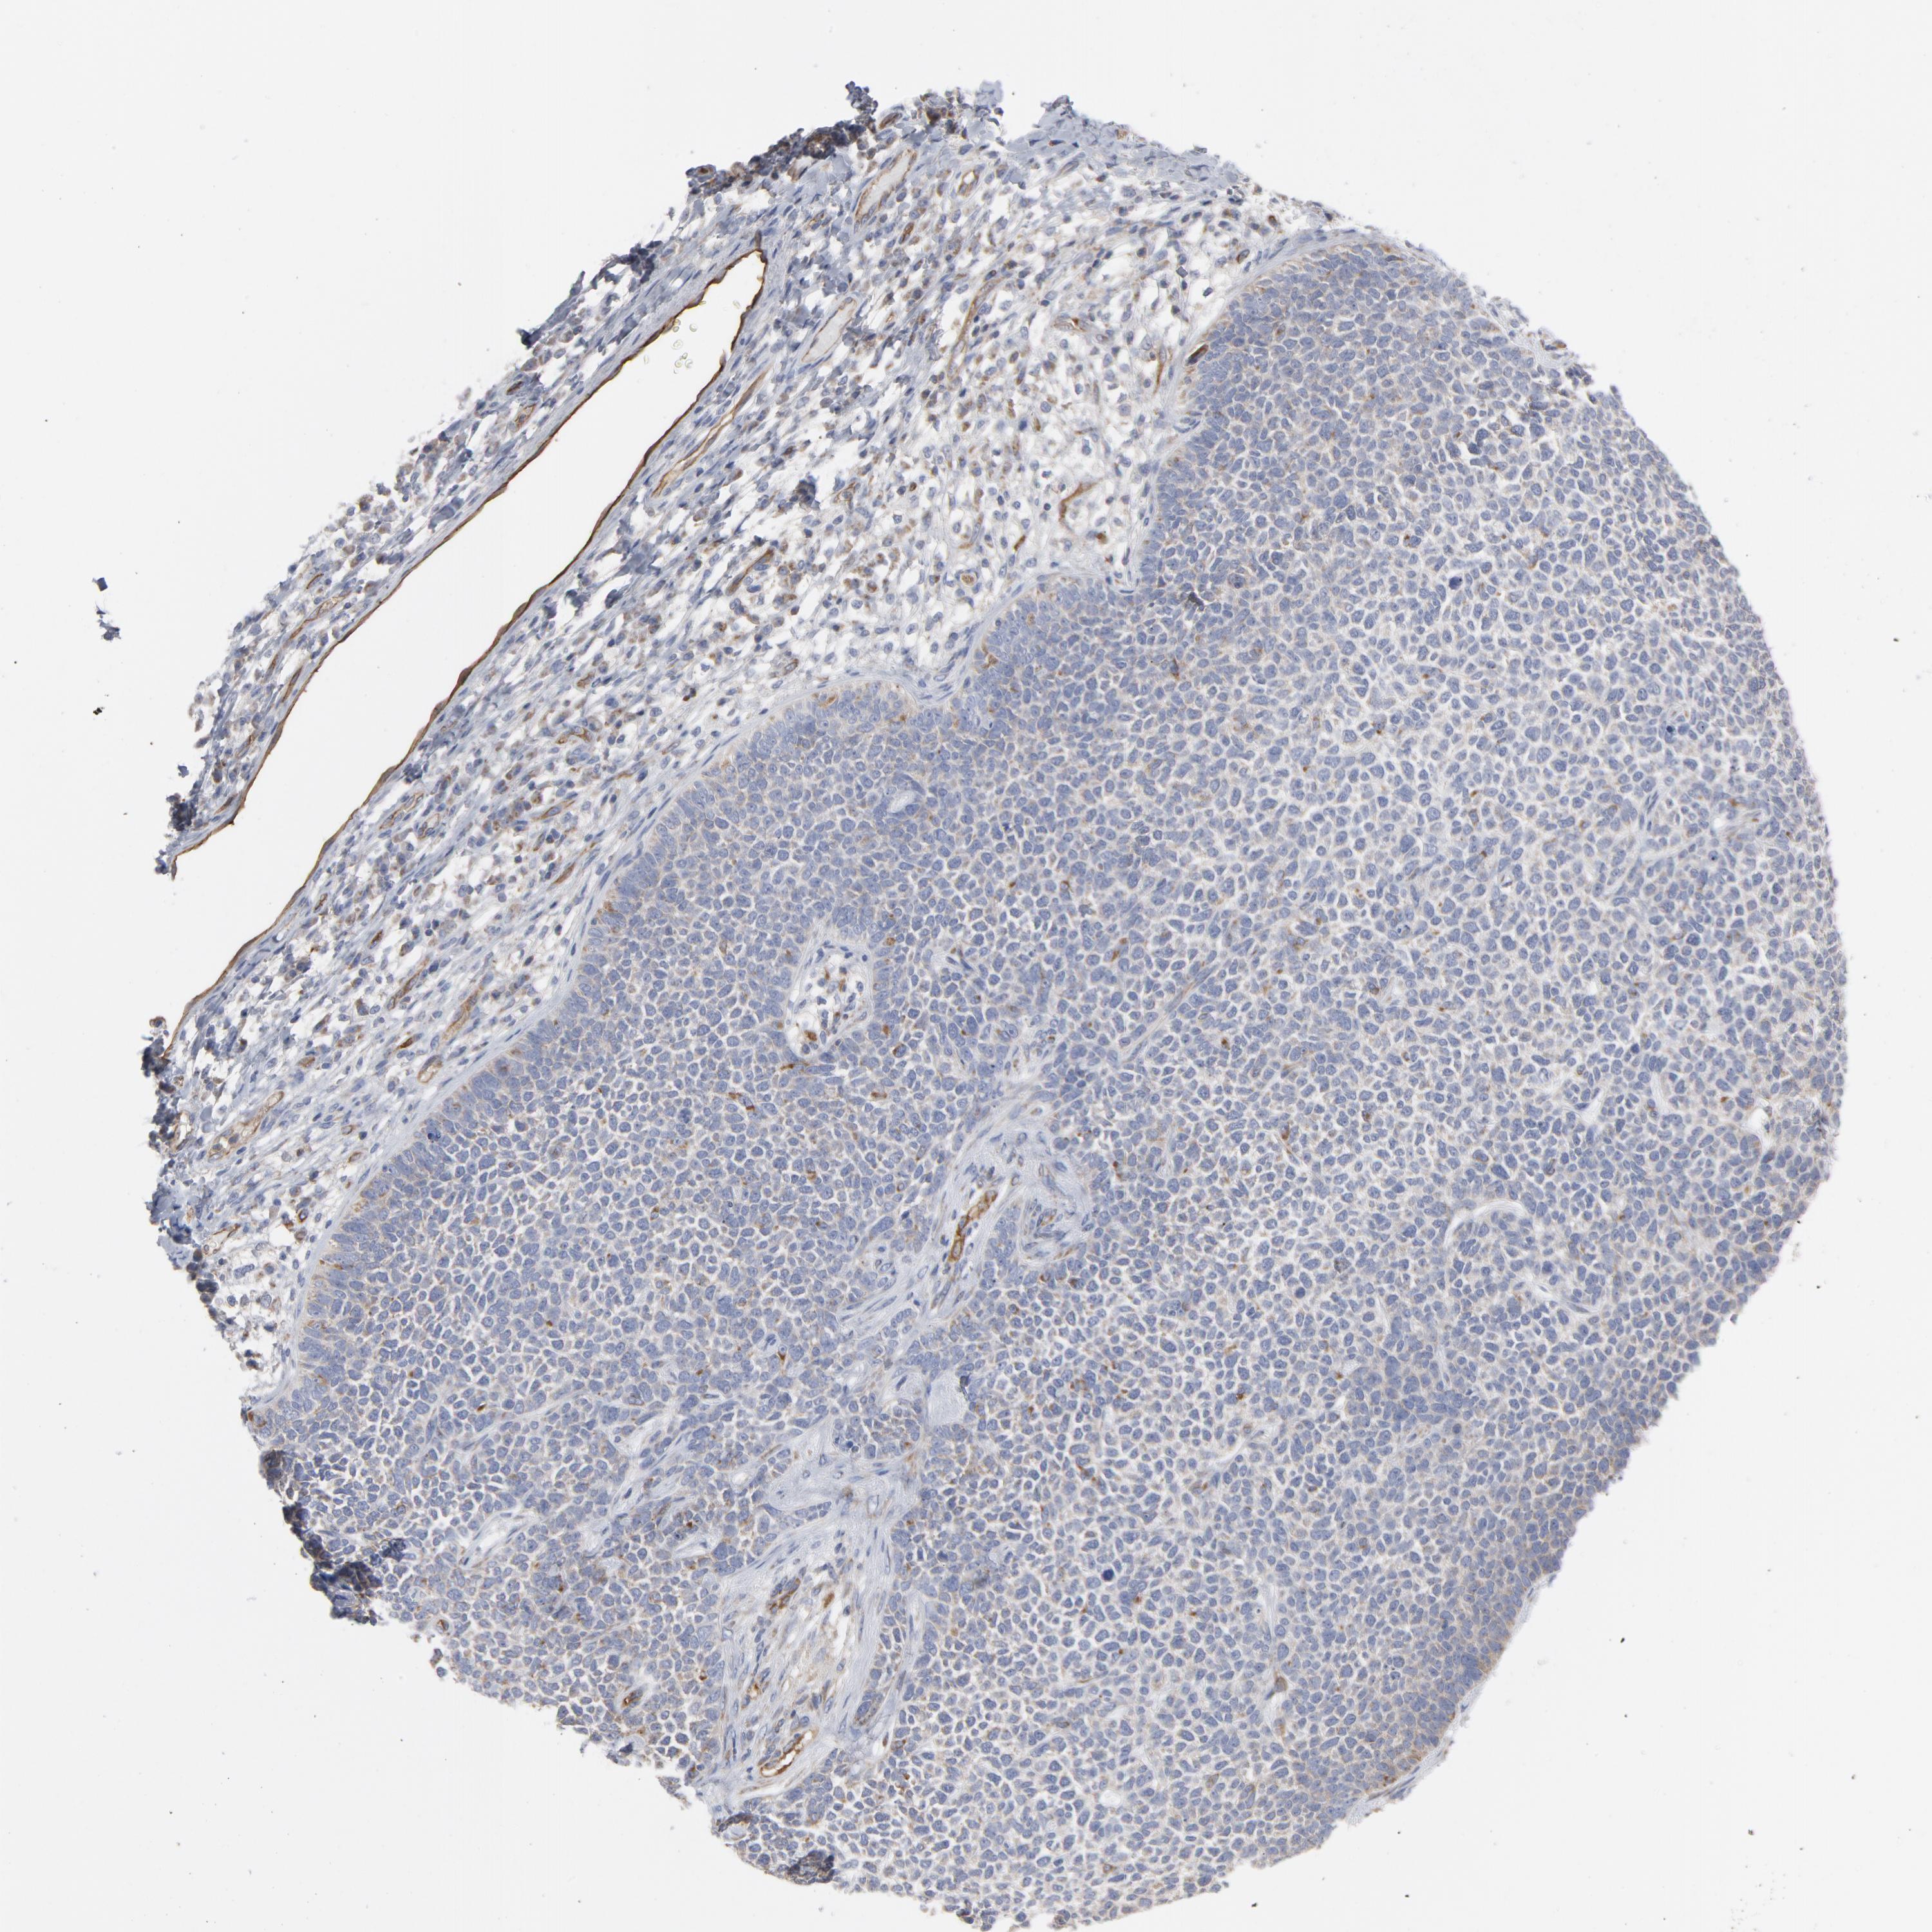

SKIN CANCER - Protein expressioni

A mouse-over function shows sample information and annotation data. Click on an image to view it in a full screen mode. Samples can be filtered based on level of antibody staining by selecting one or several of the following categories: high, medium, low and not detected. The assay and annotation is described here.

Antibody staining in the annotated cell types in the current human tissue is reported as not detected, low, medium, or high, based on conventional immunohistochemistry profiling in selected tissues. This score is based on the combination of the staining intensity and fraction of stained cells.

Each image is clickable and will lead to virtual microscopy that enables deeper exploration of all samples and also displays staining intensity scores, fraction scores and subcellular localization as well as patient and tissue information for each sample.

Antibody HPA003531

Squamous cell carcinoma, NOS

Basal cell carcinoma